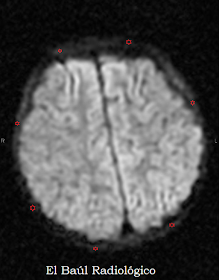

La proliferación neoplásica de la médula hematopoyética del hueso esponjoso produce un aumento de la celularidad que restringe la Difusión Isotrópica de las moléculas de agua; fenómeno físico que puede ser detectado en algunas imágenes de Tomografía por Resonancia Magnética. La restricción de la difusión que se produce en los huesos de la base del cráneo y del díploe craneal, afectados en la Leucemia Linfoblastica Aguda, se manifiesta como una Aureola intensa que contornea el tejido encefálico. Sólo es visible, este signo, en las imágenes potenciadas en Difusión Isotrópica (DWI). Es un hallazgo muy característico, aunque no exclusivo de las leucemias, que sirve también para controlar la evolución de la enfermedad.

Las siguientes imágenes corresponden a un niño de 3 años de edad diagnosticado de Leucemia Linfoblástica Aguda. La exploración se realizó para descartar infiltración leucémica del SNC.

FIGURA 9)  En las imágenes potenciadas en Difusión Isotrópica, Figuras 3,4,5,6,7,8 y 9,  se observa claramente la aureola producida por la infiltración neoplásica del díploe. (Leucemia Linfoblástica Aguda).